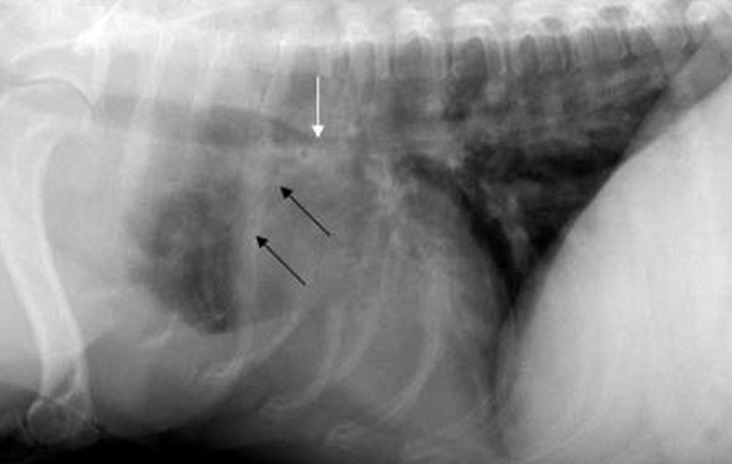

| ํก๊ธฐ ์ดฌ์ | ํธ๊ธฐ ์ดฌ์ |

|---|---|

![]() | ![]() |

| Trachea์ bifurcation๊น์ง์ ๊ธฐ๊ด ์ง๊ฒฝ์ด ๊ด์ฐฎ์ ๋ณด์. | Bifurcation ๋์๋ฝ์ด collapsed, bronchus ์ข์์ ธ ์ ๋ณด์. โ BC๋ก ์ง๋จ |

BC๋ฅผ ์ง๋จํ๊ธฐ ์ํด fluoroscopy๋ฅผ ๋ณด๋ฉด ๋์์ด ๋ง์ด ๋จ.